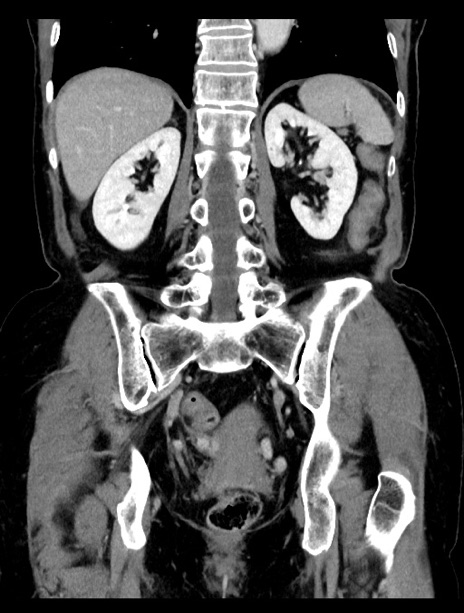

横断像

【症例】70歳代女性

【主訴】下腹部痛・嘔吐

【現病歴】2日前より腹痛あり。昨日嘔吐あり。症状改善しないため来院。

【既往歴】胃GISTに対して胃部分切除後。

【身体所見】BT 37.1℃、BP 128/77mmHg、腹部:平坦・軟、下腹部に圧痛あり。

【データ】WBC 10200、CRP 0.31